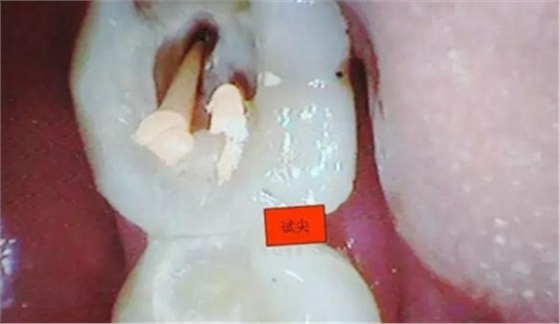

圖五

根管預(yù)備后可以確定這個是C型根管了。

4.接著與患者溝通后,同意繼續(xù)去除髓石,用細(xì)小的安全端金剛砂車針輕微的去除,沿著弧形方向切割,去除后發(fā)現(xiàn)不是2個根管口,而是一個根管口,有點(diǎn)類似下頜6遠(yuǎn)中根管口的樣子。(遠(yuǎn)中頰根16mm*15號K銼)

本病例歸類為第二類C型根管,有分開的根管,伴有異常的形態(tài),近中舌側(cè)是單獨(dú)的和明顯的。近頰根管與遠(yuǎn)中根管融合,通過一個根尖孔開口于牙根表面。開髓時要注意不要將根管在頰側(cè)的聯(lián)通誤認(rèn)為是被穿通的髓室底。